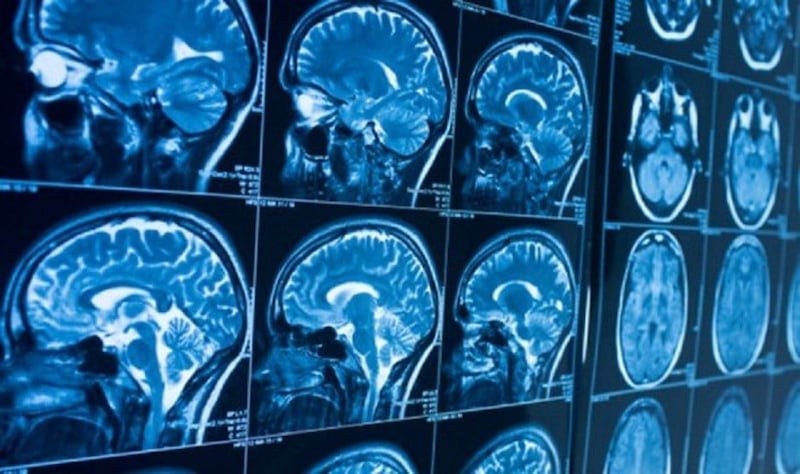

China ha intensificado su apuesta por la tecnología de Interfaces Cerebro-Computadora (BCI), lanzando un ambicioso plan para convertirse en el líder mundial de la industria de los chips cerebrales para el año 2030. Esta estrategia no solo busca adelantar a competidores occidentales como la estadounidense Neuralink de Elon Musk, sino también asegurar la soberanía tecnológica del país en el campo de la Inteligencia Artificial más avanzada.

El proyecto se presenta como un esfuerzo coordinado entre el gobierno y el sector privado, con una clara hoja de ruta que apunta a un despliegue masivo y funcional de estos dispositivos en la próxima década.

A diferencia de la narrativa centrada en Musk, el enfoque chino se centra en una aplicación dual: uso médico y tecnológico. Los implantes BCI chinos ya han demostrado capacidad para ayudar en la recuperación de lesiones cerebrales graves y mejorar la calidad de vida de personas con discapacidades.